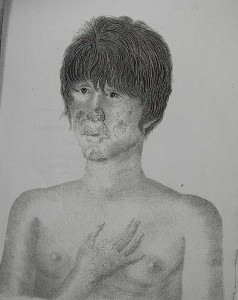

One of Losting’s famous portraits of a woman with leprosy in St Jørgen’s Hospital, Bergen, Norway

You Tube: On Leprosy (based on Danielssen and Boëck’s Atlas)

There were differences in how the disease presented itself in people living in the same area or in groups in different areas: “Cases of it differ widely in regard to form, localisation, the organs of the tissues affected, in the order, combination, duration, and intensity of the symptoms, and in the extent to which the system is affected” (135). Different individuals were affected to different degrees over different time spans: “the time of appearance, the duration, or the severity of the symptoms, may give rise to variation, and many of them may remain of secondary importance, or be altogether absent” (135). In fact, there is a problem in identifying forms of lepra because “they often pass imperceptibly into one another, or combine together, and may all be met with at once on the same individual” (135). As a result, depending on who has seen what, at what particular point in the course of the disease, certain features of the disease could be emphasised over others.

Nonetheless, they provide a detailed general symptomatology as well as descriptions of lepra tuberosa, lepra maculosa, and lepra anaesthetica, which they differentiate from syphilis, lupus, sarcoma pigmentodes, and vitiligo. Finally, they conclude their discussion of the disease with a call to end the confusion: “Let us hope that the continued co-operation of many able investigators, such as hitherto have been at work in this direction, under the stimulus of science, governments, and philanthropy, will succeed in clearing up the mystery” (193). *3